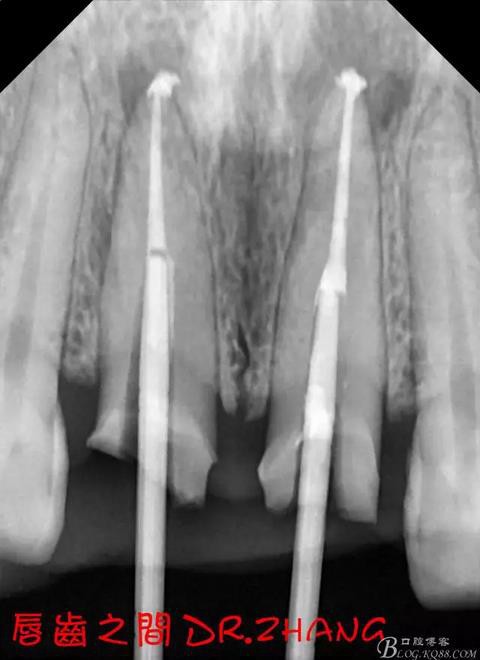

處理:21從修復(fù)體舌側(cè)打開通路 髓腔內(nèi)疑似纖維樁 高速和低速手機聯(lián)合去除樁核 在處理的過程中不斷拍片確認方向 去除樁核后拔髓針去除牙膠 只有一個標尖 膿液大量滲出 雙氧水和鹽水交替沖洗后 滲出減少 開放髓腔 隔日復(fù)診

復(fù)診:腫脹明顯消失 患者自訴感覺良好 溝通后決定拆除11 21兩顆烤瓷冠后重新修復(fù) 去冠器直接去冠 去除11根管內(nèi)的充填物 15#K銼疏通根管 11 21根長均為16MM平斷面 薩尼S3系統(tǒng)機擴至2S 期間不斷用氯己定和鹽水交替沖洗 吸潮紙尖干燥根管后06 25#試尖

思博安熱牙膠系統(tǒng)根充 燙斷至根尖三分之一處后纖維樁恢復(fù)牙體組織